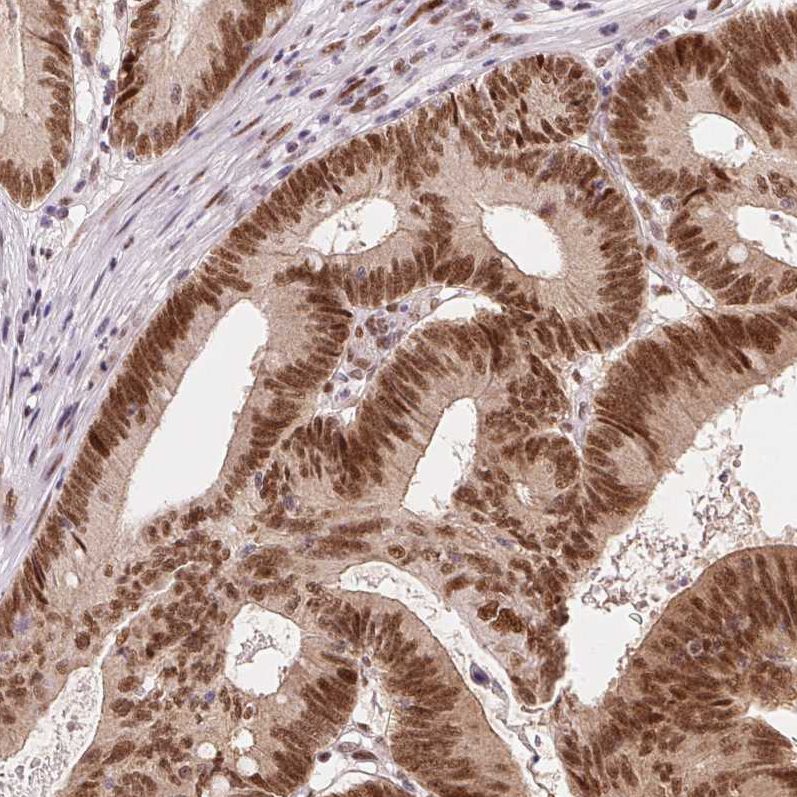

Staining of human colorectal cancer shows strong nuclear positivity in tumor cells.